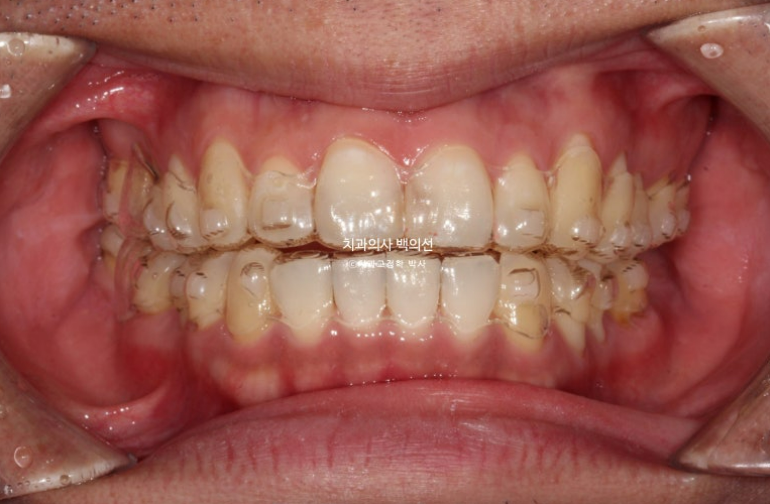

중심선 불일치와 심한 과개교합, 송곳니 덧니 등이 보입니다.

24.05~25.03

환자분이 열심히 껴준다면 10개월 만에도 좋은 결과가 나옵니다.